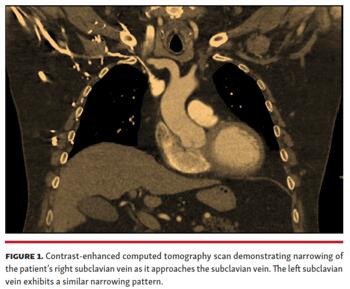

The procedure was aborted due to diminutive subclavian veins impeding access and lead placement. A chest computed tomography (CT) with contrast revealed both left and right subclavian vein narrowing, posing a barrier to conventional pacemaker implantation (Figure 1).